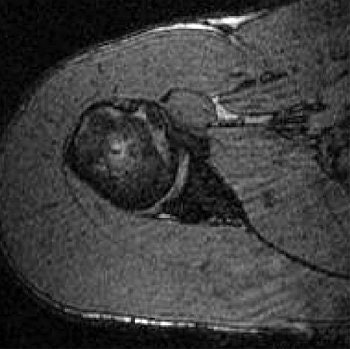

| Transverse 3D gradient-echo MR images (30/10) with volunteer in neutral position (above), unloaded ABER position at 90° external rotation (middle), and 111° external rotation (below). Note infraspinatus tendon (arrow) deformed between the greater tuberosity and posterosuperior glenoid in the loaded study. |